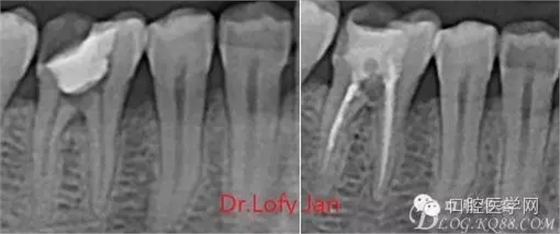

根管治療術(shù)是牙體牙髓疾病治療中最復(fù)雜和最關(guān)鍵的治療項(xiàng)目。根管充填材料抵達(dá)根尖、并能嚴(yán)密堵塞根尖孔,是確保根管治療效果的關(guān)鍵指標(biāo)。為了保證根管充填到位,醫(yī)生需要在術(shù)前照牙片以了解牙根根管的數(shù)量、彎曲程度和長(zhǎng)度,在術(shù)中有時(shí)需要插針照牙片來精確測(cè)量根管長(zhǎng)度,術(shù)后必須照牙片以確定是否根管充填到位,如果欠填或超填,就需要重新充填、重新照牙片確認(rèn),直到根管充填到位。所以,在患者接受根管治療時(shí)有時(shí)會(huì)反復(fù)照牙片。

病例分析:曲面斷層片在x線輔助診斷與檢查中目前大多數(shù)文獻(xiàn)和著作都建議只能作為初診拍片檢查手段,不能作為終末疾病的確診與手術(shù)療效的評(píng)價(jià)指標(biāo),臨床大部分中小型門診都因?yàn)樵O(shè)備不齊全導(dǎo)致信息偏差很大。